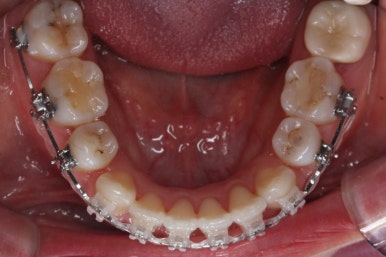

점점 개선이 되고 있는 모습이 보입니다.

정면으로 맞물렸던 교합도 좋아지고 있으며 이로 인해 자연스레 위아래의 앞뒤 간격도 맞닿게 되고 좁아지고 있습니다.

좌측에서 본 모습도 마찬가지입니다.

발치 후에 남아있던 미세한 공간도 없어졌고 윗니도 후방 이동 되면서 교합이 좋아지고 있습니다.

윗니를 봐도 미세하게 남았던 발치를 했던 공간이 없어졌습니다.

마무리 후에 다시 벌어질 수 있는 틈을 유지장치를 붙여 놓았습니다.

아랫니 모습입니다.

남아있는 발치의 공간이 없어졌으며 큰 이동이 없이 마무리가 되었습니다. 안쪽에는 발치공간이 다시 벌어지지 않도록 유지철사를 길게 연장해서 붙였습니다.